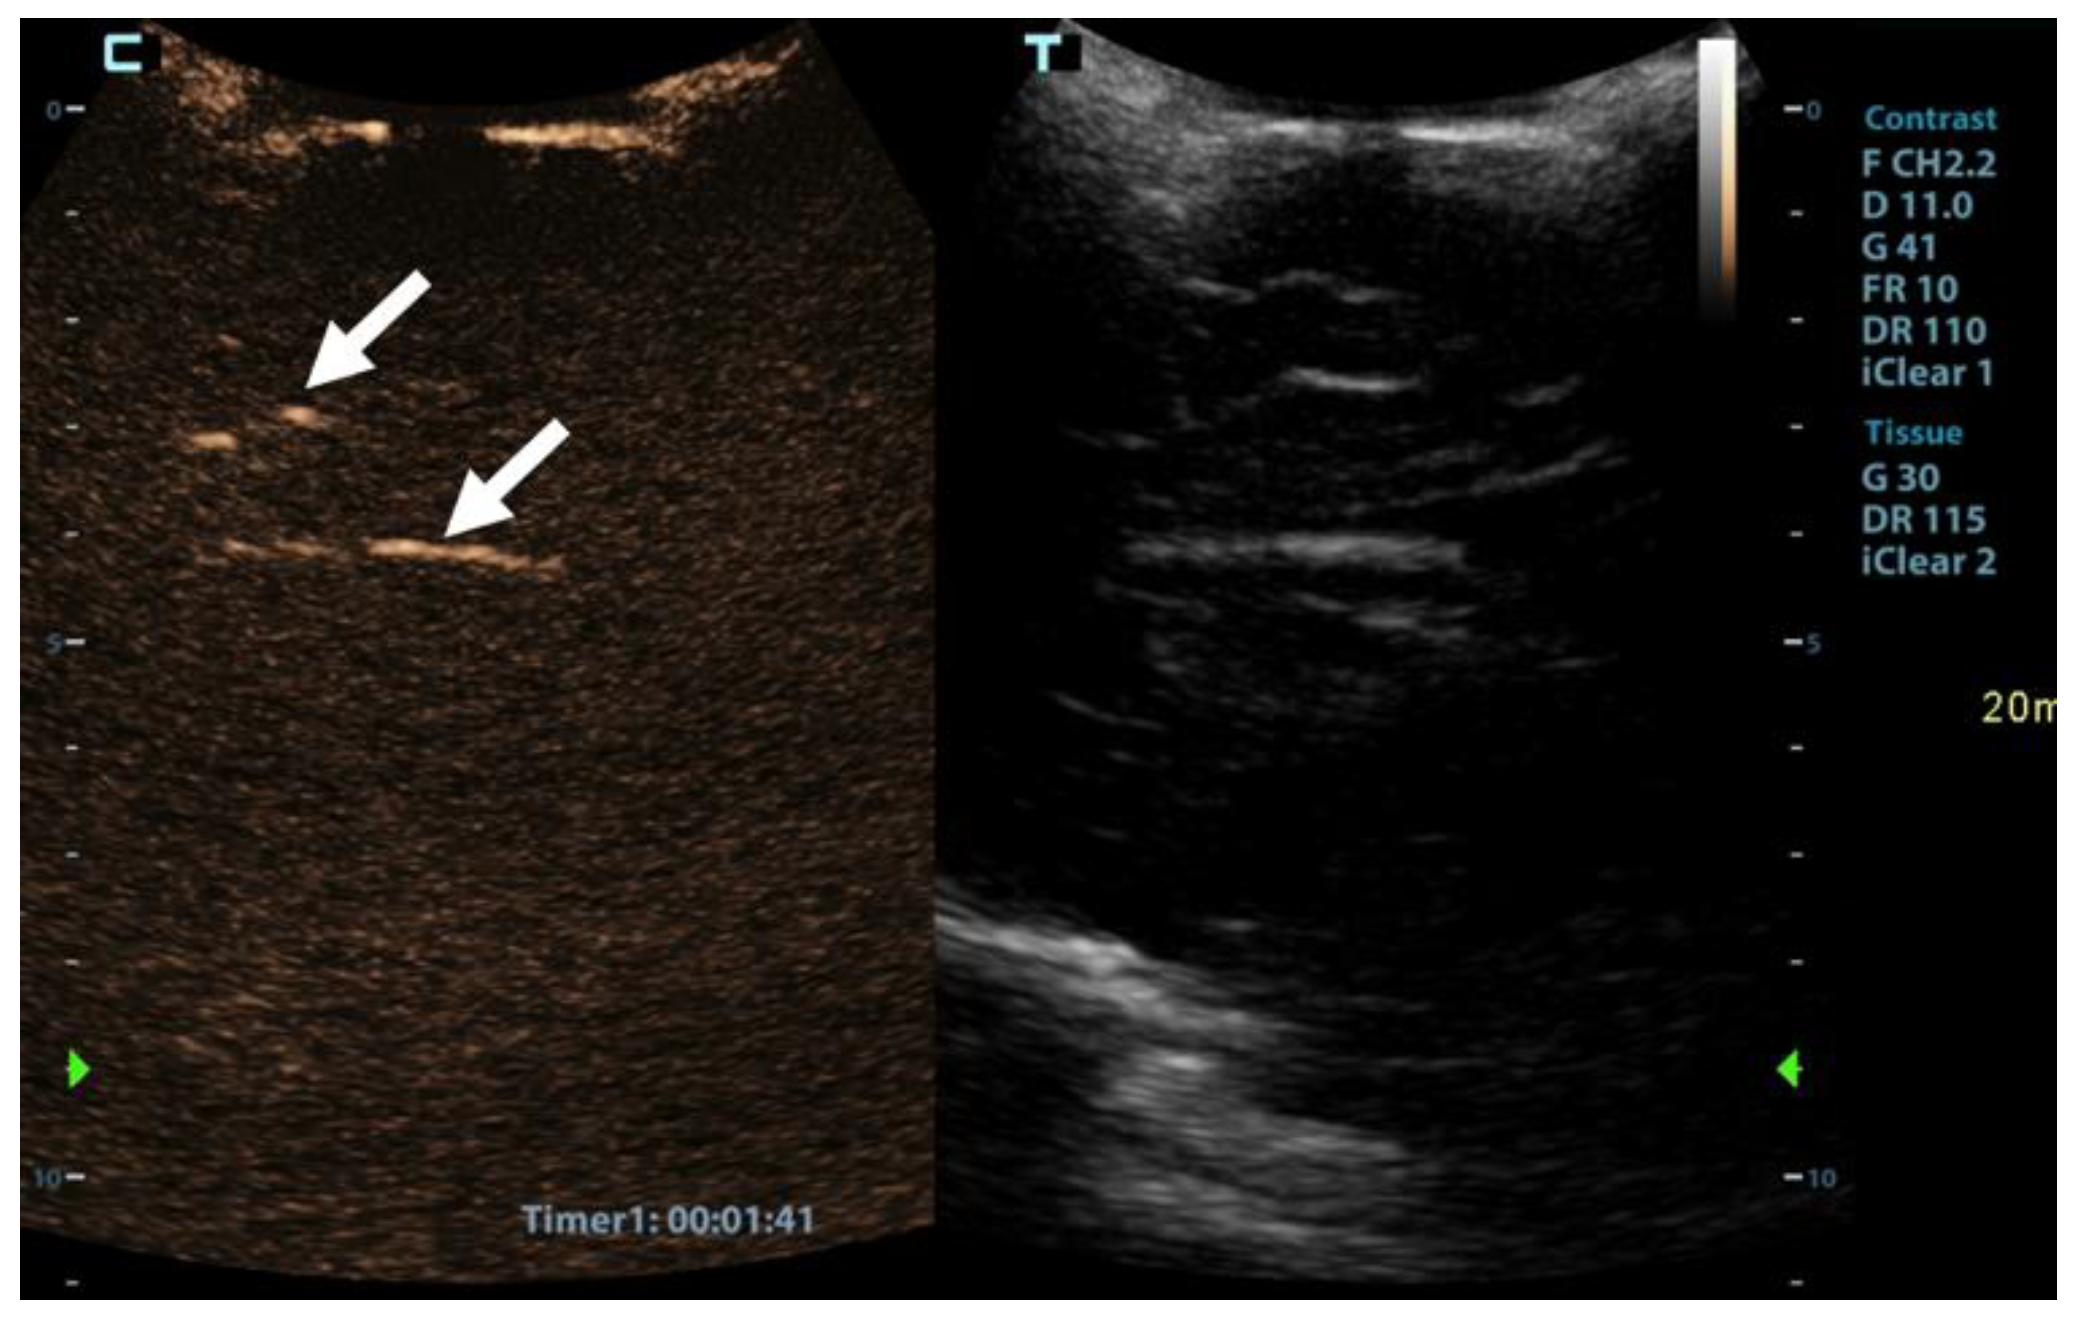

CEUS was performed as an ancillary imaging test for the confirmation of brain death. Before the examination, the details of the examination and the risks for the patient were explained to the child’s guardian. Written informed consent was obtained from the child’s guardian to perform the brain CEUS scan. The examination was performed by a paediatric radiologist with 2 years of subspecialty experience in paediatric brain imaging and 4 years of experience in performing CEUS examinations. For the examination, a Mindray M9 ultrasound scanner with a 1.4–5.1 MHz convex ultrasound transducer was used (Mindray, Shenzhen, China). SonoVue (Bracco, Milan, Italy) was used as the contrast agent. The anterior fontanelle was used as the acoustic window to scan the brain in the coronal and sagittal planes. Firstly, pre-contrast grey-scale imaging was performed to optimise the image. After that, a contrast-specific imaging mode and a low dynamic mechanical index (MI) of 0.06–0.07 was used for the scanning during the CEUS examination. To enable the simultaneous attachment of the US contrast agent and saline to the line, to avoid any delays in flushing the line with a saline flush, a three-way stopcock was connected to the existing peripheral intravenous line. At the start of the examination, 0.3 mL of US contrast agent, followed by a saline flush, was intravenously applied through a peripheral line. Only one bolus of US contrast agent was administered during the examination. For the first 60 s after the contrast administration, a continuous cine clip was obtained in the coronal plane at the level of the third ventricle, including the frontal horns of the lateral ventricles and heads of the caudate nuclei bilaterally. After that, intermittent images were obtained during the next 10 min in order to assess brain perfusion and avoid excessive contrast microbubble destruction from continuous imaging. The CEUS examination showed enhancement of the extracranial vessels and a lack of enhancement of the intracranial vessels (Figure 2). Only a scant amount of contrast microbubbles was observed within the left middle cerebral artery and pericallosal artery during the examination (Figure 3). After 10 min, we observed complete microbubble clearance and finished with the examination. The brain CEUS examination was performed in a paediatric intensive care unit at the bedside, and the whole procedure, including preparation, lasted approximately 15 min. No adverse effects were observed after the intravenous application of US contrast agent.

Figure 3. Sagittal contrast-enhanced ultrasound image of a 1-year-old infant’s brain obtained 101 s after contrast administration. The image demonstrates a scant amount of contrast microbubbles within the pericallosal artery and its branch (arrows) and no brain perfusion.